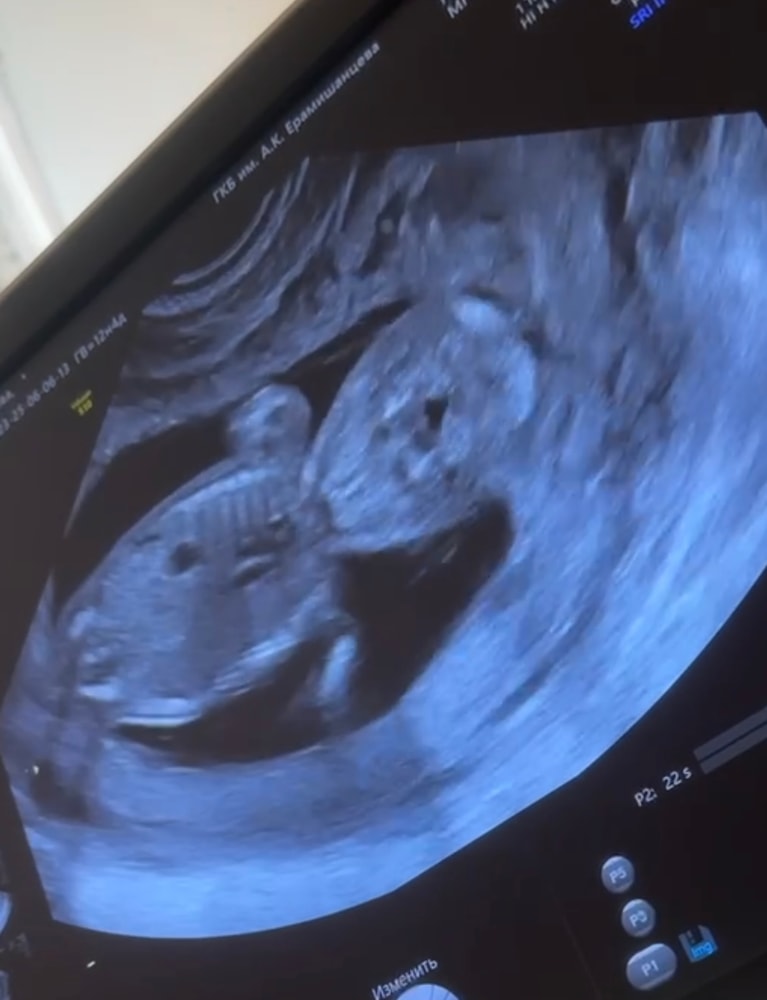

3 фото - голова, спинка и ручки